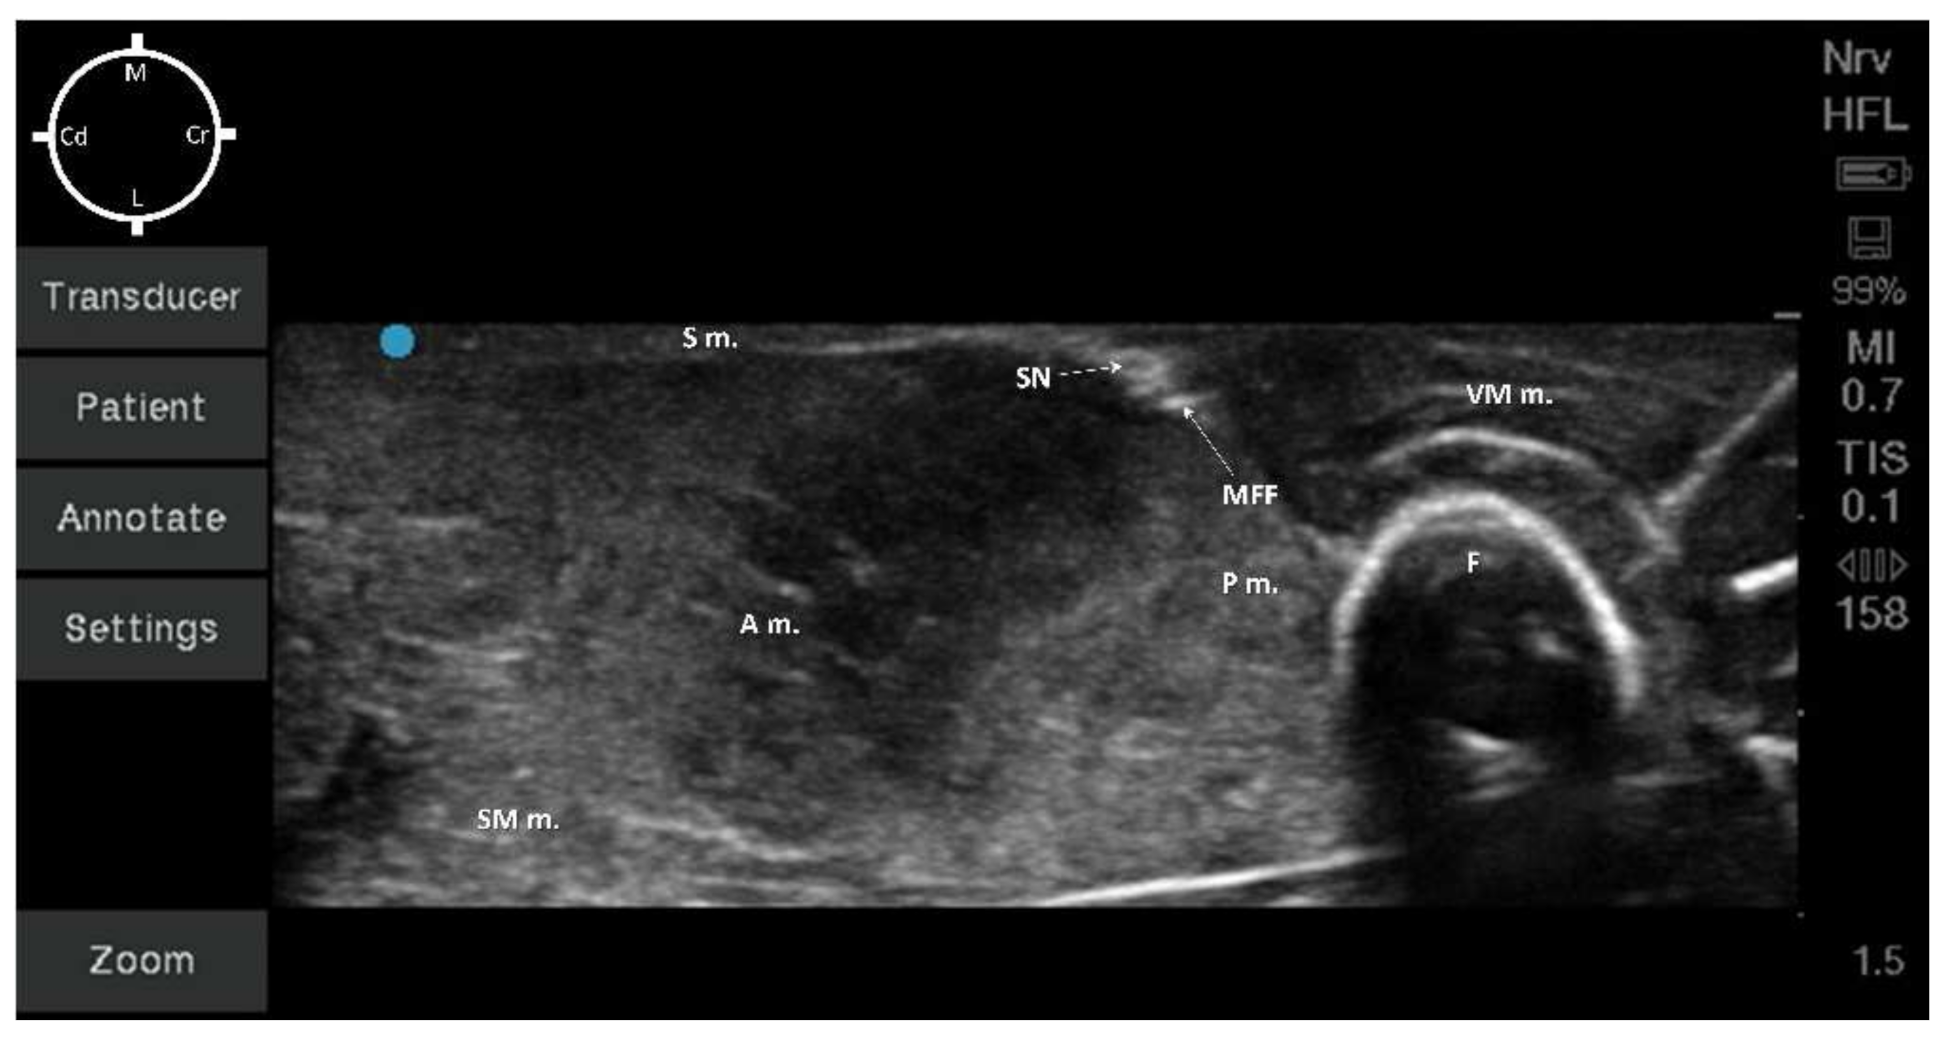

2.2. Sono-Anatomy Study and US-Guided Saphenous Nerve Block Design

3.2. Sono-Anatomy Study and US-Guided Saphenous Nerve Block